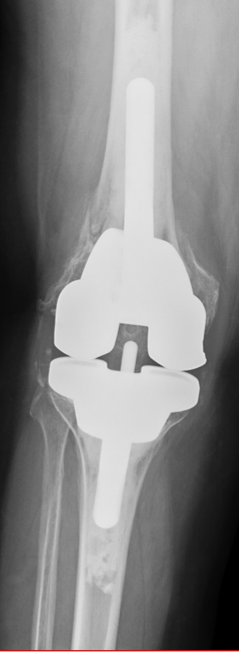

Case: 61 yo F w/ painful right revision TKA after a fall. Elevated serum Co, Cr. Not infected. Treatment of the femur? Management of well-fixed TM tibial cone?

Signficant metallosis in the joint and osteolysis about the femoral condyles. Cement-in-cement revision to DFR with retention of well-fixed TM tibial cone. Data on outcomes of retained, well-fixed cones coming in 2023!